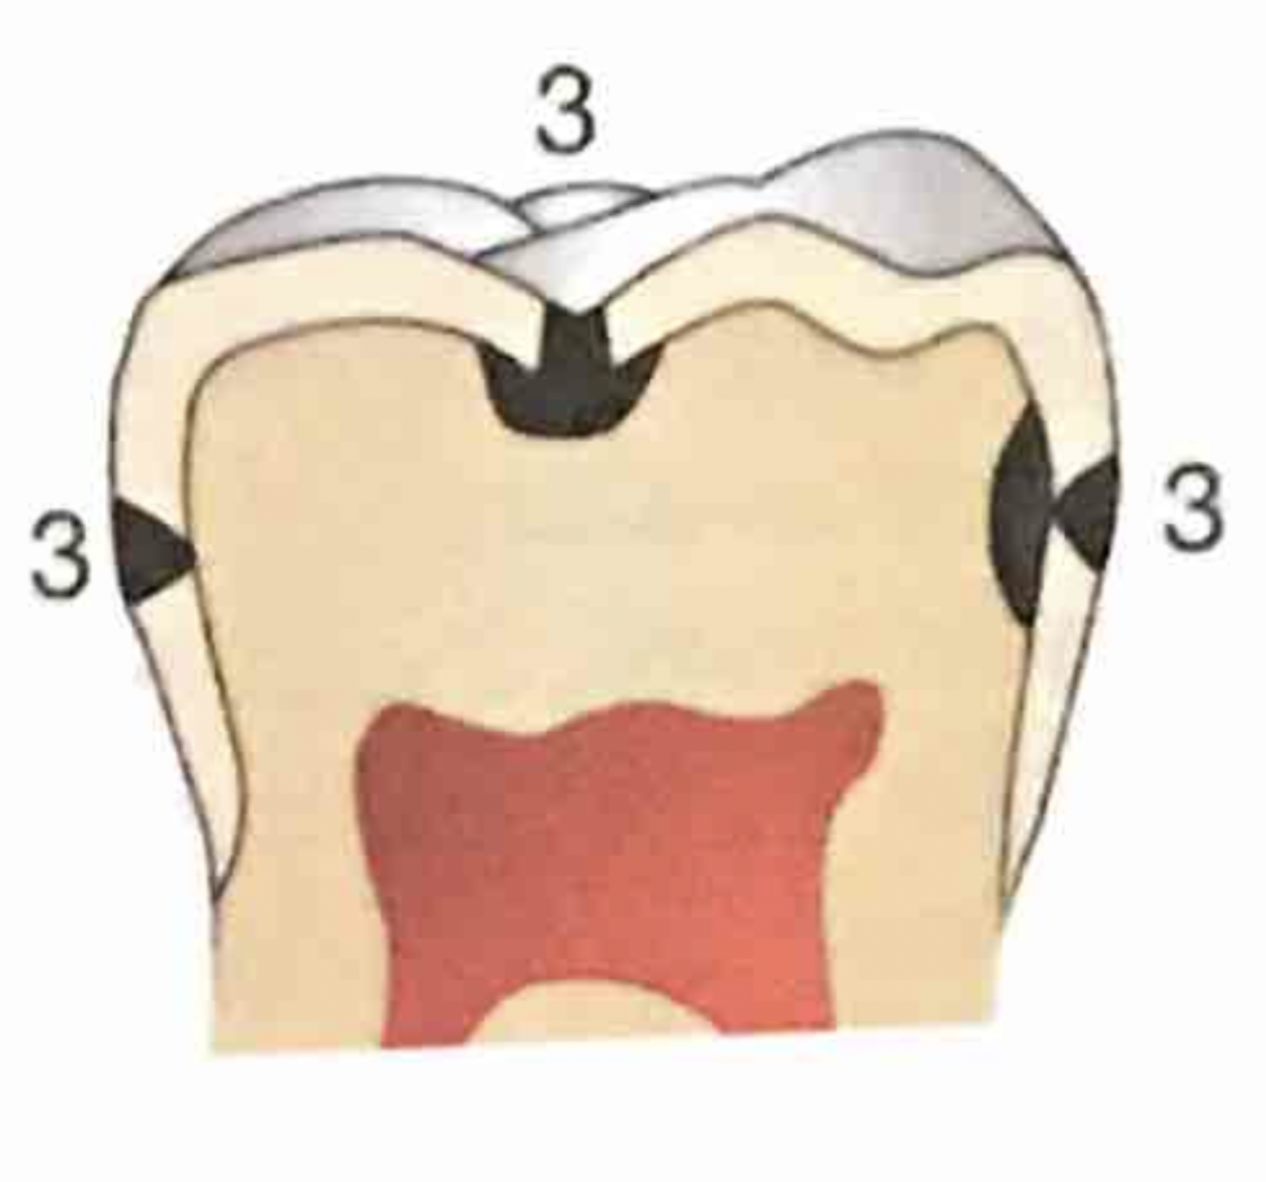

Name the classification of dental caries illustrated by 3

C-3 Advanced Caries

Advanced: Lesion that extends to or through the DEJ but does not extend more than half the distance to the pulp